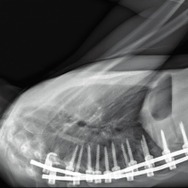

パリ北部近郊の5つの病院のオペ室を舞台に、医師視点のカメラや内視鏡の映像を使い、脳や⼤腸、眼球など様々な外科⼿術や帝王切開の模様を医師の視点で⾒つめたドキュメンタリー。